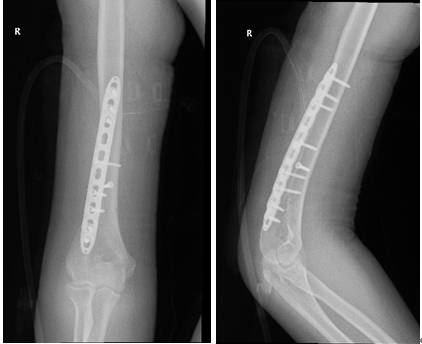

在完善术前准备后,厦门市中医院骨伤科何发胜主任、刘胜主任及唐聪医师团队为小强做了骨折切开复位钢板螺钉固定手术。小强手术后需休养康复至少3个月,学业肯定得受影响了。

小强术后的X光片,可以看见用于固定的钢板。

同时在肱骨干的桡神经走行与肱骨关系密切,肱骨中下段骨折时极易损伤桡神经。如果神经损伤则更为严重,可导致支配区域的手腕部感觉麻木和活动障碍。骨折和神经损伤多需要手术切开复位,并用钢板螺钉固定。